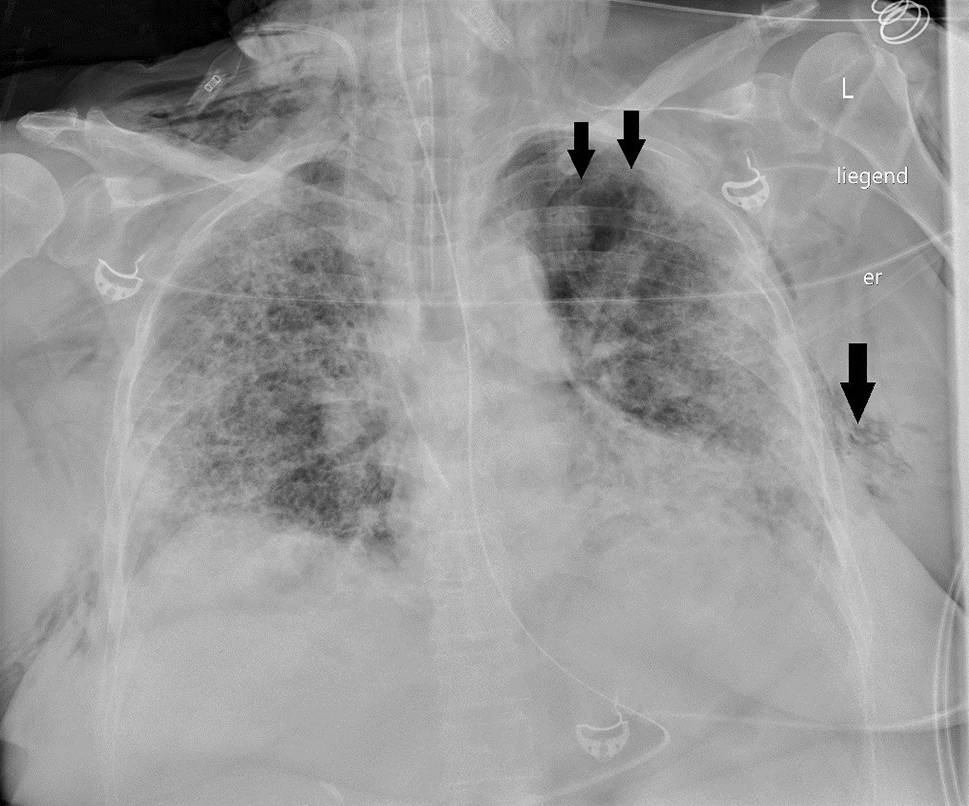

Die Kreislaufparameter waren bis auf leichte Tachykardie von 95/min unauffällig, die Patientin war afebril. Bei erhöhter Atemfrequenz von 28/min betrug die periphere Sauerstoffsättigung 87 % unter 10 l O2/min Maskenatmung. Im Labor bestanden Leukozytose von 9,5 G/l sowie Erhöhung von CRP auf 85,7 mg/l, von Ferritin auf 1062 ng/ml und von (IL)‑6 auf 225 pg/ml. In Thorax-CT zeigten sich bilaterale, diffus flächig konfluierende Milchglasverdichtungen (Abb. 7). Nach Einleitung von antibiotischer Therapie und Kortisongabe gelang es zunächst mit nichtinvasiven Beatmungsverfahren, einen Oxygenationsindex von 150 zu halten. Am Tag 6 wurden jedoch Intubation und Beatmung unumgänglich. Am Tag 13 fand sich erstmals ein Weichteilemphysem links thorakal und rechts supraklavikulär. Die Thoraxröntgenaufnahme (Abb. 8) zeigte zusätzlich zum Weichteilemphysem einen schmalen, apikalen Pneumothorax links, der umgehend drainiert wurde. Danach war das Weichteilemphysem regredient. Nach erfolgreichem Weaning von der Beatmung („dual positive airway pressure“, Spitzrendrücke 30 mbar, durchschnittlicher „driving pressure“ 15 mbar für insgesamt 19 Tage) wurde die Patientin am Tag 26 aus der Intensivbehandlung entlassen und am Tag 54 mit residualem, intermittierendem Sauerstoffbedarf von 3 l/min in die externe Rehabilitation transferiert.

Abb. 7

Bilaterale Lungenfibrose nach COVID-Pneumonie. Pneumatozele im rechten Unterlappen (Pfeil)

Abb. 8

Weichteilemphysem (lange Pfeile), apikaler Pneumothorax links (kurze Pfeile)